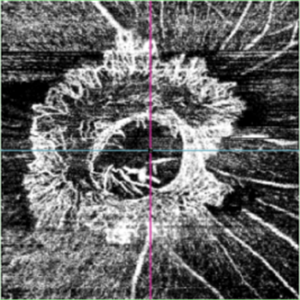

OCT Angiography of Optic Disc ( vitreous slab) of a 56 year old male with proliferative diabetic retinopathy showing neovascularization of disc.

Imaging device: TOPCON DRI OCT Triton Plus swept source OCT

Condition/keywords: NEOVASCULARISATION OF DISC, OCTA